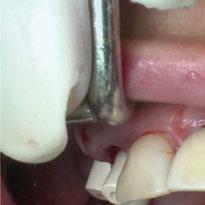

y lo que se pudo preservar del hueso malar. Se añadió una malla sinterizada infraorbitaria para dar volumen a la mejilla y se planificaron dos brazos de conexión que emergieran en las posiciones 24 y 26 de forma subgingival (Figuras 8 y 9). La superficie interna que apoyaba en el hueso era de titanio microrrugoso, y la superficie externa y conectores de titanio pulido y hexágono externo universal (Figuras 10 y 11). La cirugía se hizo bajo anestesia general en infiltración con anestesia local (4% articaína, 1:100.00 epinefrina), levantando el

colgajo cutáneo de la mejilla por vía intraoral, preservando el colgajo temporal para no comunicar con el remanente de la cavidad naso maxilar (Figura 12). Se emplearon 10 tornillos de osteosíntesis de 1,9 mm y la estabilidad primaria obtenida fue excelente (Figura 13)

4 meses después de la cirugía la encía estaba completamente cicatrizada y las conexiones de los implantes tipo hexágono externo universal quedaron a nivel yuxtamucoso. En este caso no se requirió el empleo de pilares transepiteliales y las impresiones fueron tomadas

directamente a cabeza de implante para realizar una prótesis dentoalveolar de cerámica de 3 piezas, que equilibraran la oclusión y dieran soporte al labio y la mejilla (Figuras 14-17)